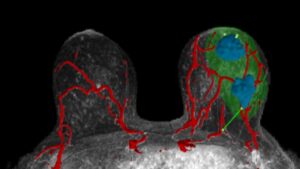

A new AI-powered, imaging-based technology that creates accurate three-dimensional models of tumors, veins and other soft tissue offers a promising new method to help surgeons operate on, and better treat,...